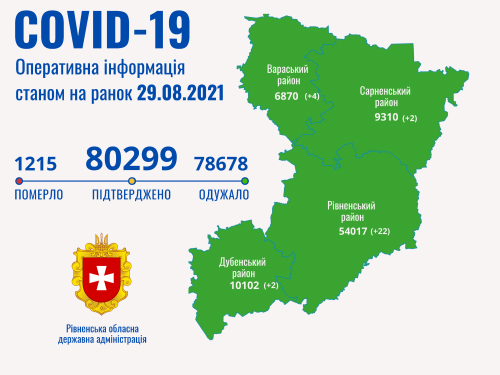

Коронавірус повертається: як стрімко зростає кількість хворих на Рівненщині (ВІДЕО)